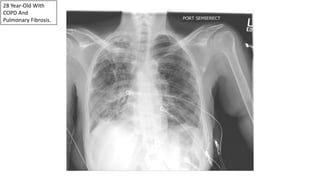

28 Year-Old With

COPD And

Pulmonary Fibrosis.

Recurrent Left Apical Pneumothorax